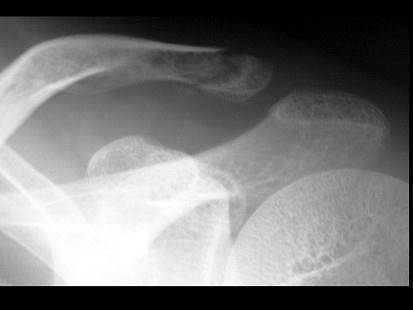

男,25岁,外伤后摄片,请结合影像图像选择最可能的诊断 ( )A、肋骨骨折伴气胸B、锁骨骨折伴气胸C、锁骨骨折D、原发性气胸E、肋骨骨折

问题 男,25岁,外伤后摄片,请结合影像图像选择最可能的诊断 ( )

选项 A、肋骨骨折伴气胸 B、锁骨骨折伴气胸 C、锁骨骨折 D、原发性气胸 E、肋骨骨折

答案 C